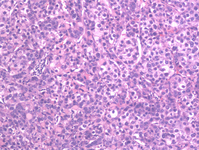

Medium power microscopic view of a hematoxylin and eosin stained section depicting normal liver on the right and HCC on the left. A sharp boundary separates the distinct zones of normal liver and tumor